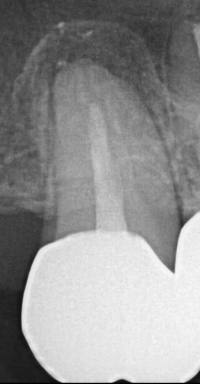

Root canal is a common treatment for severely damaged or infected. The procedure involves removing the diseased pulp from the tooth, cleaning and disinfecting the root canals, and then sealing the space. While many patients successfully retain their root canal-treated teeth for years, there are cases where removal might be recommended. Let’s explore the benefits of removing a root canal-treated tooth, the potential risks associated with retaining it, and the overall impact on health.

- Elimination of Infection Risks: Despite the best efforts during a root canal, bacteria can harvest in the small dentinal tubules where the tooth may continue to harbor infections, potentially leading to further complications. Removing the tooth can eliminate this source of infection, preventing it from spreading to other parts of the body.

- Chronic Infection: If a root canal is not entirely successful, or if there is an issue with the restoration, it can lead to chronic infection. Symptoms like persistent pain, swelling, or recurrent abscesses can be signs that the tooth might still be harboring harmful bacteria.

- Weakened Tooth Structure: After a root canal, the tooth can become more susceptible to fractures or breakage due to the loss of its internal structure. A tooth that has become structurally compromised may require more extensive restorations or could potentially fail over time.